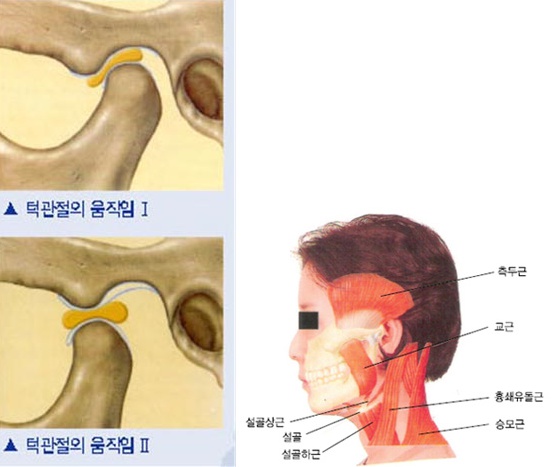

턱관절은 아래턱뼈, 머리뼈, 그 사이의 관절원판(디스크),인대, 주위 근육등의 근골격계로 이루어졌으며 귀 앞쪽에 위치한 관절입니다. 턱관절장애란 턱관절과 관련되어 생기는 장애를 말하며 두통을 포함한 머리-목 부위의 동통을 포함하는 경우가 대부분이어서 측두하악장애 또는 두개하악장애라고도 합니다.

턱관절장애는 크게 턱관절 자체의 장애와 두경부 근육장애(긴장성 두통포함)로 나눌 수 있으며, 일반적인 증상들은 턱관절의 동통, 이통, 두통, 안면통을 호소하며 아래턱의 운동제한, 비대칭적인 아래턱의 운동형태, 관절잡음(관절음, 거대관절음, 마찰음등), 이갈이, 이 악물기 등이 있습니다. 통증 및 관절잡음 그리고 개구제한을 턱관절장애의 3대 증상이라고 합니다.